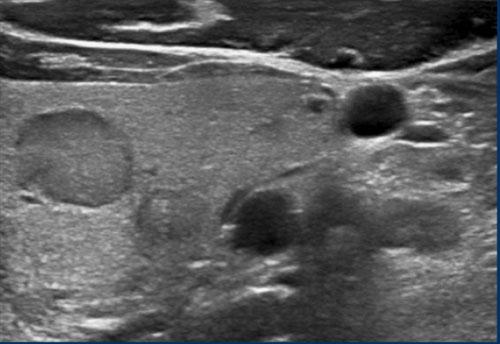

Trường hợp 2

Quan sát hình ảnh và xác định điểm TI-RADS.

Cuộn hình ảnh để xem điểm TI-RADS.

Nốt này giảm âm so với mô tuyến giáp bình thường có thể nhìn thấy ở mặt bụng của nốt.

Điểm TI-RADS: 2 điểm cho độ hồi âm giảm âm.